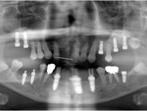

Case.02 オールオン4症例

初診時

上顎の残存歯を保存してインプラント治療を行った場合は、インプラント本数が多くなり、臼歯部への骨造成も必要となるため、しっかり噛めるようになるまでに約9ヶ月間かかります。患者さんが早期回復を要望されたため、残存歯を戦略的に抜歯してAll-on-4(オールオンフォー)による即日完了治療を選択しました。

(下顎のインプラント治療は他院で行われたものです)

レントゲン